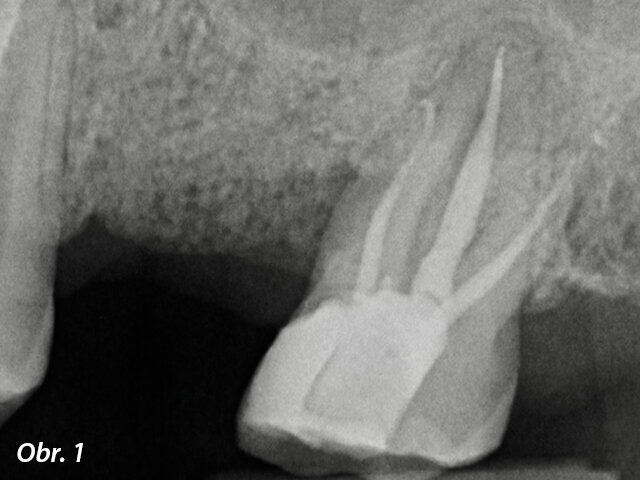

Klinický případ, kterým dále uvádím, je skvělým příkladem toho, jak obtížné je určit původ pacientových symptomů pouze na základě intraorálního snímku. Vizualizace 2D snímku selhává v jistotě určení přítomnosti léze, ještě důležitější však je, že je nemožné určit velikost, morfologii a typ léze, kterou se podaří nalézt. Analýza 3D snímku nám poskytne jasnou představu o klinické situaci: koronální a sagitální řezy odhalily přítomnost veliké léze sahající od apexu meziálního kořene tohoto moláru do furkace, zatímco axiální řezy nám umožňují provést přesnou analýzu endodontické anatomie a obzvláště pak tvaru meziálního kořene, který byl v tomto případě spojen s palatinálním kořenem. Celkový přehled o situaci ovlivňuje rozhodování o postupu a stanovení léčebného plánu zahrnujícího speciální úkony (obr. 1–4).